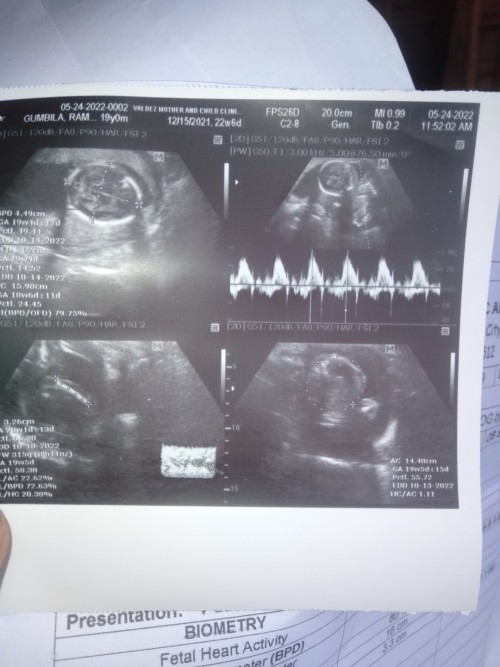

Ultrasound Picture sharing my 9wks 2days RAINBOW BABY 🌈

Congrats sis ❤ #TeamDecember

10wks #teamdecember ❤️

5months and 6days 🤗